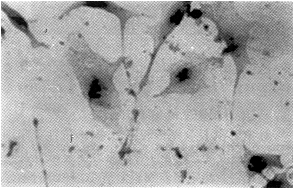

原位杂交及免疫组化显示,转染反义TGF-β1的贮脂细胞表达的FN、ColA1阳性细胞数及阳性程度明显低于未转染及空载体转染的贮脂细胞(图2~4)。

图2 未转基因细胞ColA1免疫组化染色为强阳性 SP×200

图3 转基因细胞ColA1免疫组化染色为弱阳性 SP×200

图4 未转基因细胞TGF-β1原位杂交为强阳性 SP×200